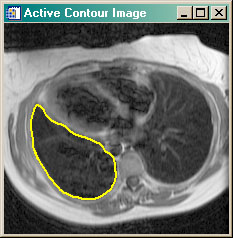

- ACTIVECONTOUR Active contour (or snake) example program. Uses GVF Active Contouring algorithm.